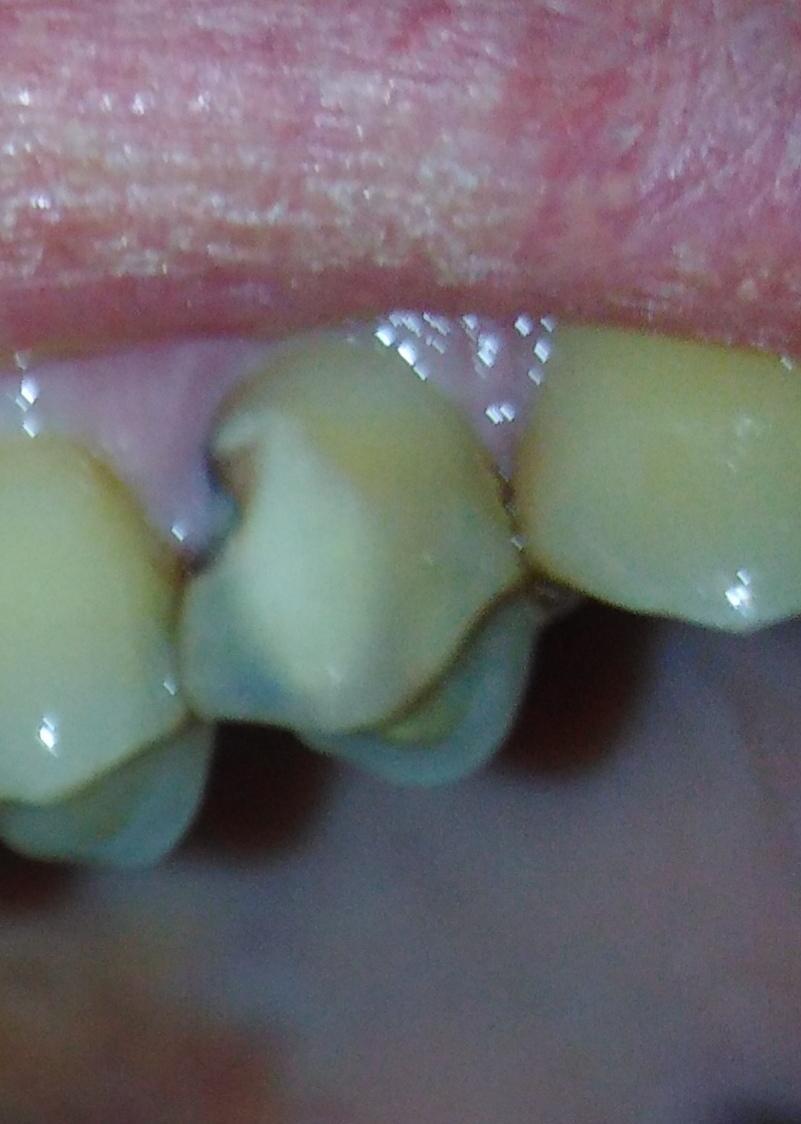

Доктор предлагает удалить, сначала пробовала - сверлила, сказала тонкие стенки, глубокий кариес ( вроде как под десну пошел) и не сделать коронку. Не могу сомневаться в квалификации доктора, вроде старается сохранить зубы до конца, рядом 1.6 развалившуюся которую в нескольких клиниках сразу на удаление посылали - реставрировала, 1.5 все хотели пульпитировать оставила живым залечив но здесь ни в какую хотя зуб выглядит и страшновато но не болит же. Снимки правда из кт 8 мес. назад - что есть если надо другую пропорцию - скину.